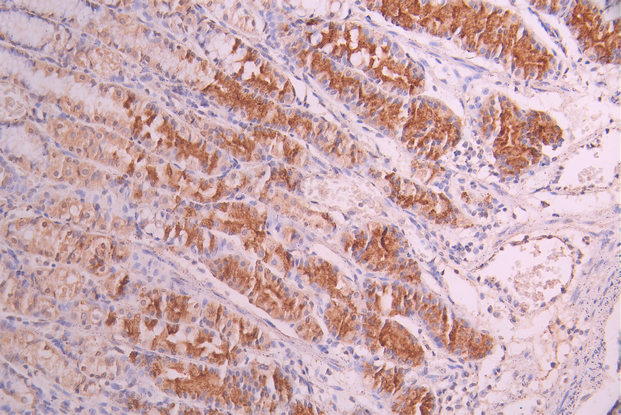

IHC image of CSB-RA005621MA1HU diluted at 1:50 and staining in paraffin-embedded human gastric cancer performed on a Leica BondTM system. After dewaxing and hydration, antigen retrieval was mediated by high pressure in a citrate buffer (pH 6.0). Section was blocked with 10% normal goat serum 30min at RT. Then primary antibody (1% BSA) was incubated at 4°C overnight. The primary is detected by a Anti-Human lgG, Fcy Fragment Specific labeled by HRP and visualized using 0.05% DAB.